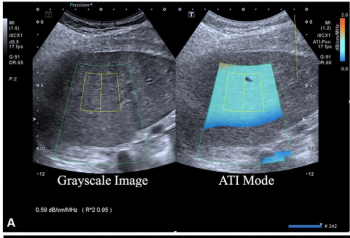

Emerging research suggests that combining full-field digital mammography and whole-breast ultrasound tomography provides superior sensitivity in detecting BI-RADS 4 lesions and superior specificity in diagnosing BI-RADS 3 lesions than mammography alone in women with dense breasts.